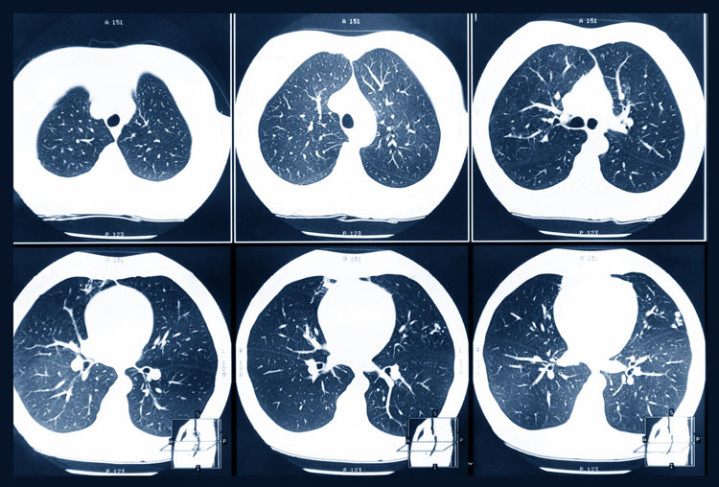

第二天就请假去了病院查验,成果发现结节照旧增长到了14mm,且出现了实性身分。后续的增强CT、肿瘤标记物查验高度怀疑是恶性肿瘤,刘先生被安排住院进行干系协调。好在刘先生的病程还处于早期,不错进行手术协调,术后他很快就康复出院了。

有这几种特征的肺结节,恶性进度很高,要多加警惕:

• 大小:体积越大的结节危境进度就越高

• 数目:相同性质的结节,数目越多的恶性进度会比数目少的要高

• 长相:结节有毛刺征、分叶状、血管集束征、胸膜凹下征等特征,恶性进度较高

• 位置:处于肺叶处的结节风险性较高,中下肺叶的则危境进度较低

• 变化:在发现结节后,医师会提出如期进行复查,复查历程中发现结节变大或是步地发生了改变,齐要警惕可能是恶变了

• 密度:从危境进度上来看,是搀杂型>磨玻璃>实性